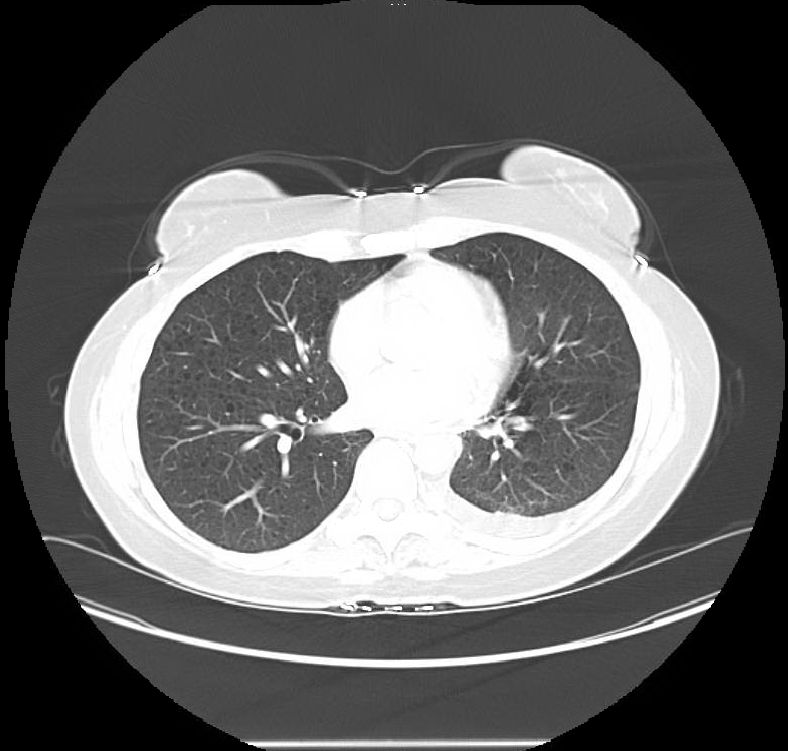

Case Presentation: A 41-year-old female presented with non-productive cough and worsening exertional shortness of breath for 3 weeks. She denied fever, night sweats, orthopnea, paroxysmal nocturnal dyspnea. There was no history of recent travel, smoking, or illicit drug use. She did not have any significant past medical or family history. On physical exam, there was dullness to percussion and diminished breath sound on the left side. Basic blood work including complete blood count and serum chemistry were within normal limits. Chest x-ray confirmed a large left sided pleural effusion. A Computerized tomography (CT) scan of the chest done for further workup revealed numerous thin-walled small cystic lesions in bilateral lung fields along with a large left sided pleural effusion. The patient underwent diagnostic as well as therapeutic thoracentesis. One liter of milky fluid was removed by thoracentesis. Pleural fluid analysis showed lymphocytic predominance (68%), and had a triglyceride level of 2363 mg/dL. Cytology and flow cytometry of the pleural fluid was negative for malignant cells and lymphoproliferative disorders respectively. Based on the clinical presentation and radiological findings, a diagnosis of lymphangioleiomyomatosis was made. Serum vascular endothelia growth factor-D levels were also tested, and came back at 2000 pg/mL. The patient reported of doing better within a week of starting treatment with sirulimus, and has not had a recurrence of her effusion since then.